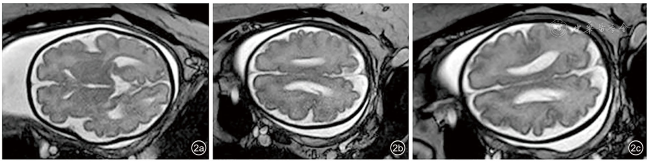

图2 孕30周胎儿多小脑回畸形(双侧)的MRI表现。图a可见外侧裂形态可;图b、c可见脑沟回增多,见众多浅细脑沟

孕妇35岁,孕3产1,夫妻均体健,非近亲结婚,否认孕前、孕期毒物与放射线接触史,否认家族遗传病史。2023年3月开始于深圳市妇幼保健院规律产检。自然受孕,经早孕期孕8周超声核对末次月经及预产期无误。停经12周胎儿超声提示:胎儿大小相当于13+4周,颈项透明层厚度(nuchal translucency,NT)1.7 mm,胎儿鼻骨可见,心脏声像改变提示右位主动脉弓。经遗传学咨询后,于16+2周行羊膜腔穿刺,采集胎儿羊水进行染色体核型分析+染色体微阵列分析,结果均未见异常。孕22+1周行Ⅲ级超声检查:胎儿大小相当于25+1周。胎儿右位主动脉弓,左锁骨下动脉迷走,左位动脉导管,其与左锁骨下动脉相连,动脉导管、左锁骨下动脉及主动脉弓三者形成“U”形血管环,局部气管受压,受压段宽约0.17 cm,其上段宽约0.27 cm。胎儿头围位于均数+3.49标准差,腹围位于均数+3.02标准差,体重位于第99.95百分位[参考美国国家儿童健康与人类发展研究所(National Institute of Child Health and Human Development,NICHD)曲线],胎儿左侧侧脑室宽约0.96 cm。胎儿永久性右脐静脉。由于胎儿超声出现新表型“大头畸形”及“过度生长”,原有羊水DNA进一步检测甲基化特异性多重连接探针项目排查Beckwith-Wiedemann综合征,结果为阴性;孕妇拒绝同时行家系全外显子组测序(whole exome sequencing,WES)。孕26周孕妇诊断为“妊娠期糖尿病”。孕26+1周复查超声提示胎儿头围进行性增大:胎儿头围位于均数+4.96标准差,腹围位于均数+2.88标准差,体重位于第99.95百分位,胎儿左侧侧脑室宽约0.92 cm。再次告知原有羊水检测项目的局限性,夫妻知情同意原有羊水DNA进一步行WES,结果提示,在PIK3CA基因上检出与胎儿临床表型相符的可能致病变异:NM_006218.4:c.1346C>T(p.Pro449Leu)杂合变异,经夫妻双方外周血验证均为野生型,为新发变异。孕妇于孕29+6周再次复查超声提示:胎儿大小相当于35+2周,胎儿头围位于均数+6.2标准差,胎儿颅脑声像改变:巨头畸形、多小脑回(图1a~1c)、外侧裂及顶枕沟浅(图1d、1e),脑实质分层明显(图1f)、左侧脑室宽1.3 cm。胎儿右位主动脉弓,左锁骨下动脉迷走并“U”形血管环形成。胎儿永久右脐静脉。孕30周行胎儿头颅MRI检查提示(图2):胎儿巨头,多小脑回畸形,双侧脑室增宽,胎儿额枕径位于均值+4标准差以上水平,双顶径、骨双顶径、胼胝体长度位于均值+3标准差以上水平,小脑蚓部前后径位于均值+2标准差以上水平,小脑蚓部高度位于均值+7标准差以上水平。根据多次超声及MRI结果,胎儿可诊断为脑皮质发育畸形(malformations of cortical development,MCD),综合基因检测结果及产前影像学表现,提示胎儿预后不良,孕妇及家属知情并于孕31+3周引产,胎儿出生体重2940 g,头围34 cm,胸围33 cm,腹围33 cm,身长49 cm,外观未见明显异常,未行胎儿尸解。本病例报道通过深圳市妇幼保健院伦理委员会批准(批件号:KYYS-2025-039)。